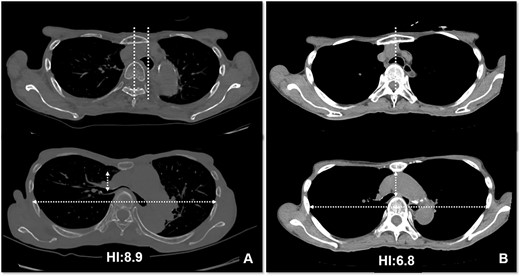

Based on these imaging tests, surgery for oropharyngeal cancer caused breathing difficulties due to a leftward shift of the trachea. The sternum’s depression led to severe narrowing of the right main bronchus, and age-related factors added to the respiratory distress. We performed a Nuss procedure for PE repair to release the stenosis of the right main bronchus surgically. As thoracoscopy revealed a depressed sternum, we corrected the sternal depression by sternal elevation using two pectus bars. Postoperative chest CT showed improvement in the sternal depression (HI:4.6, Fig. 3B) and right main bronchial stenosis (Fig. 4B). Furthermore, shortness of breath was relieved postoperatively.

Pre- (A) and postoperative (B) CT findings: the Nuss procedure improved the chest wall and right main bronchus stenosis, and reduced HI from 8.9 to 4.6.